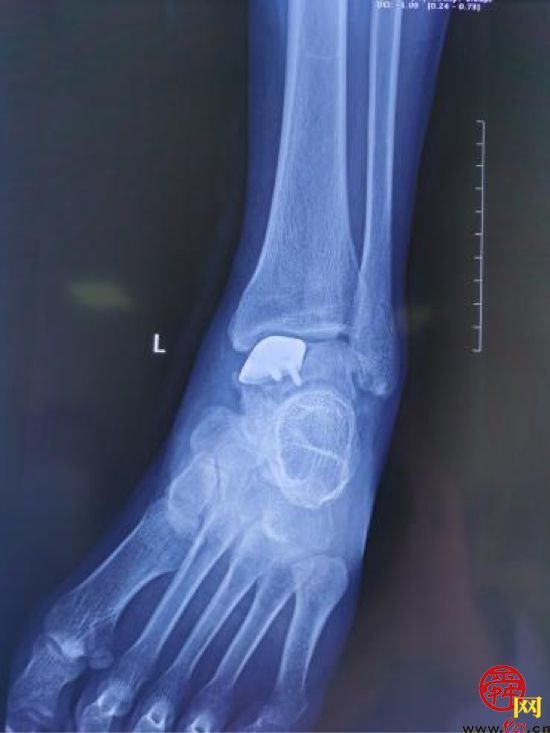

患者,男,28岁,左踝关节疼痛1年,加重3个月,影像学表现为左距骨内髁坏死、塌陷,面积约3*2cm大小。距骨坏死的治疗,对直径在2cm以内的距骨坏死,可以采用自体股骨髁骨软骨移植、自体带骨膜髂骨移植等方法,但对于直径超过2cm的距骨坏死,尤其是年轻患者,一直是治疗的难点。搜索国内外文献,对于超过2cm距骨坏死,一般采用踝关节融合、踝关节置换、同种异体距骨移植、全距骨置换等方法。但上述方法均有弊端:采用关节融合,患者丧失踝关节功能;踝关节置换、全距骨置换对于年轻、距骨单髁坏死患者,创伤大,且需要多次的返修手术;国外有采用同种异体新鲜距骨移植的报道,但目前国内还没有相关的骨组织工程库。经手术团队术前充分讨论,认为3D打印技术因其个性化的设计已经越来越多地应用于临床,决定对患者行3D打印距骨部分置换手术。

(术前患者的影像情况)